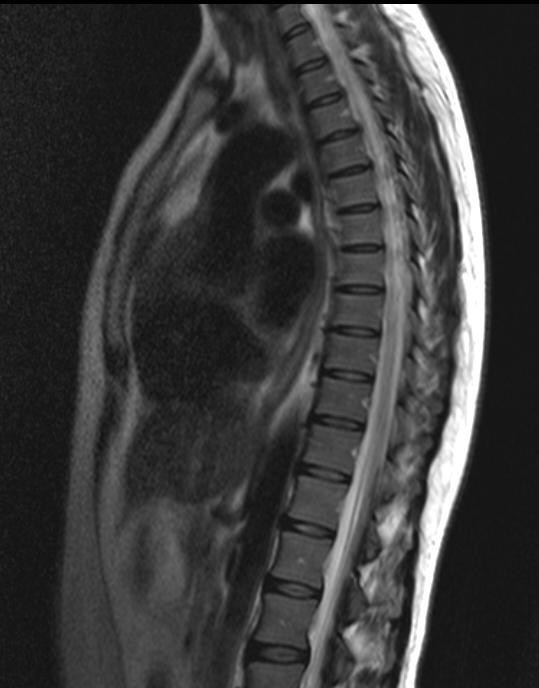

Дамы, подскажите где в Киеве можно сделать МРТ позвоночника? Я начала гуглить и растерялась, от выбора клиник до цен, слишком много информации🙈 может кто-то делал недавно и доволен? Интересует правый берег желательно

Меддиагностика, на Дарнице! Все понравилось! Оборудование такое же как и в МР24. Мр 24, по личному опыту, не рекомендую. Там пропустили глиому зрительного нерва, размером в 2.7 см.

М24 хорошее качество делают